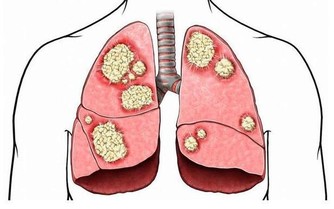

早在青少年時期,關節軟骨就開始退化,

骨關節炎開始趁機蠢蠢欲動。

隨著年齡增長,血液循環及肌肉變弱,

關節部位因潤滑液分泌減少而變干,

軟組織的彈性減弱,更易受到拉傷的威脅,

同時軟骨變得易砰易剝落;

半月板也開始退化並缺乏重建的能力,

這個問題因體重增加而惡化。